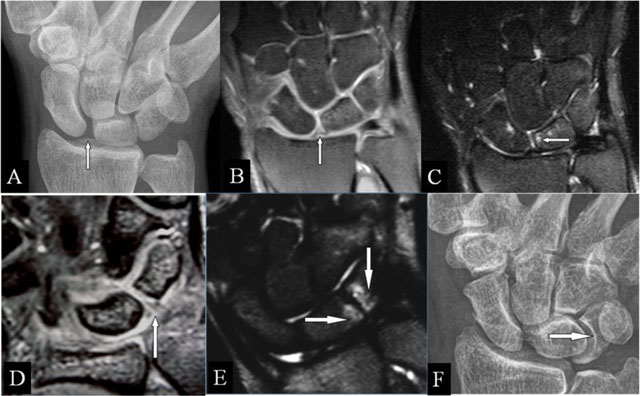

Ulnolunate and/or ulnotriquetral abutment

In secondary positive ulnar variance, the latter abuts the lunate and/or triquetral bone and eventually leads to ulnar head deformation (Figure 4A–B). It may be associated with a TFCC tear. A lengthening of more than 3 mm may be symptomatic (Hulten criteria) [12]. TFCC lesions and BMO typically at the proximal-ulnar corner of the lunate bone are revealed early by MRI (Figure 4C–E).

Figure 4

Ulnolunate and/or ulnotriquetral abutment. (A, B) PA plain radiographs; (C, D) Coronal SE PD-WI FS; and (E) Coronal SE T2-WI FS. (A) Ulnolunate abutment with a sclerotic defined impression at the ulnar side of the lunate bone. (B) Ulnotriquetral abutment with sclerotic bordered neoarticulation. (C–E) Ulnolunate abutment with chondromalacia at the ulnar border of the lunate bone (D, vertical arrow), subchondral cyst (D, oblique arrow), and bone marrow oedema centered at the ulnar side of the lunate bone (E).

Ulnar translation with abutment

Extensive destruction of extrinsic ligaments leads to a proximal-ulnar carpal shift [13], creating a reversed status compared to ulnar abutment (ulna approaches carpus). The lateral widening of the radioscaphoid joint and the lunate position versus its corresponding articular fossa (less than 50% overlap in neutral position) are hallmarks on radiographs (Figure 5A). MRI presents the cartilage destruction, BMO, and eventual TFCC lesions (Figure 5B and C).

Figure 5

Ulnar translation with abutment. (A) PA plain radiograph; (B) Coronal SE T1-WI; and (C) Coronal SE PD-WI FS. (A–C) Lateral widening of the radioscaphoid joint (oblique arrow) and the lunate bone overlapping less than 50% with the corresponding radial articular fossa due to the ulnar translation of the carpus. (B, C) Cartilage destruction, oedema, and an accompanying lesion of the TFCC.